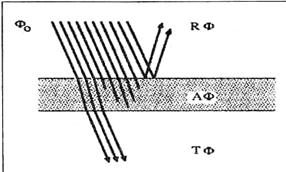

При попаданні лазерного променя на тканину можуть спостерігатися три процеси: відбиття, поглинання і/або пропускання - тільки незначний відсоток випромінювання відбивається безпосередньо від поверхні (рисунок 1.1).

Рисунок 1.1 - Оптичні властивості прошарку матерії. Падаючий променевий потік розділяється на три частини: відбита частина Rф, поглинена частина Аф і пропущена частина Тф: Рф+Аф+Тф=1

Промені, що проникають в тканину, частково поглинаються, частково розсіюються і частково пропускаються (рисунок 1.2).

Рисунок 1.2 - Оптичні властивості лазерного променя на шкірі